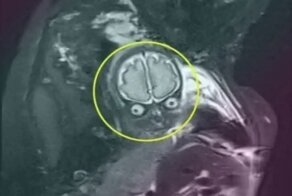

- "Весь в отца!": как выглядят внутриутробные снимки детей, сделанные с помощью МРТ